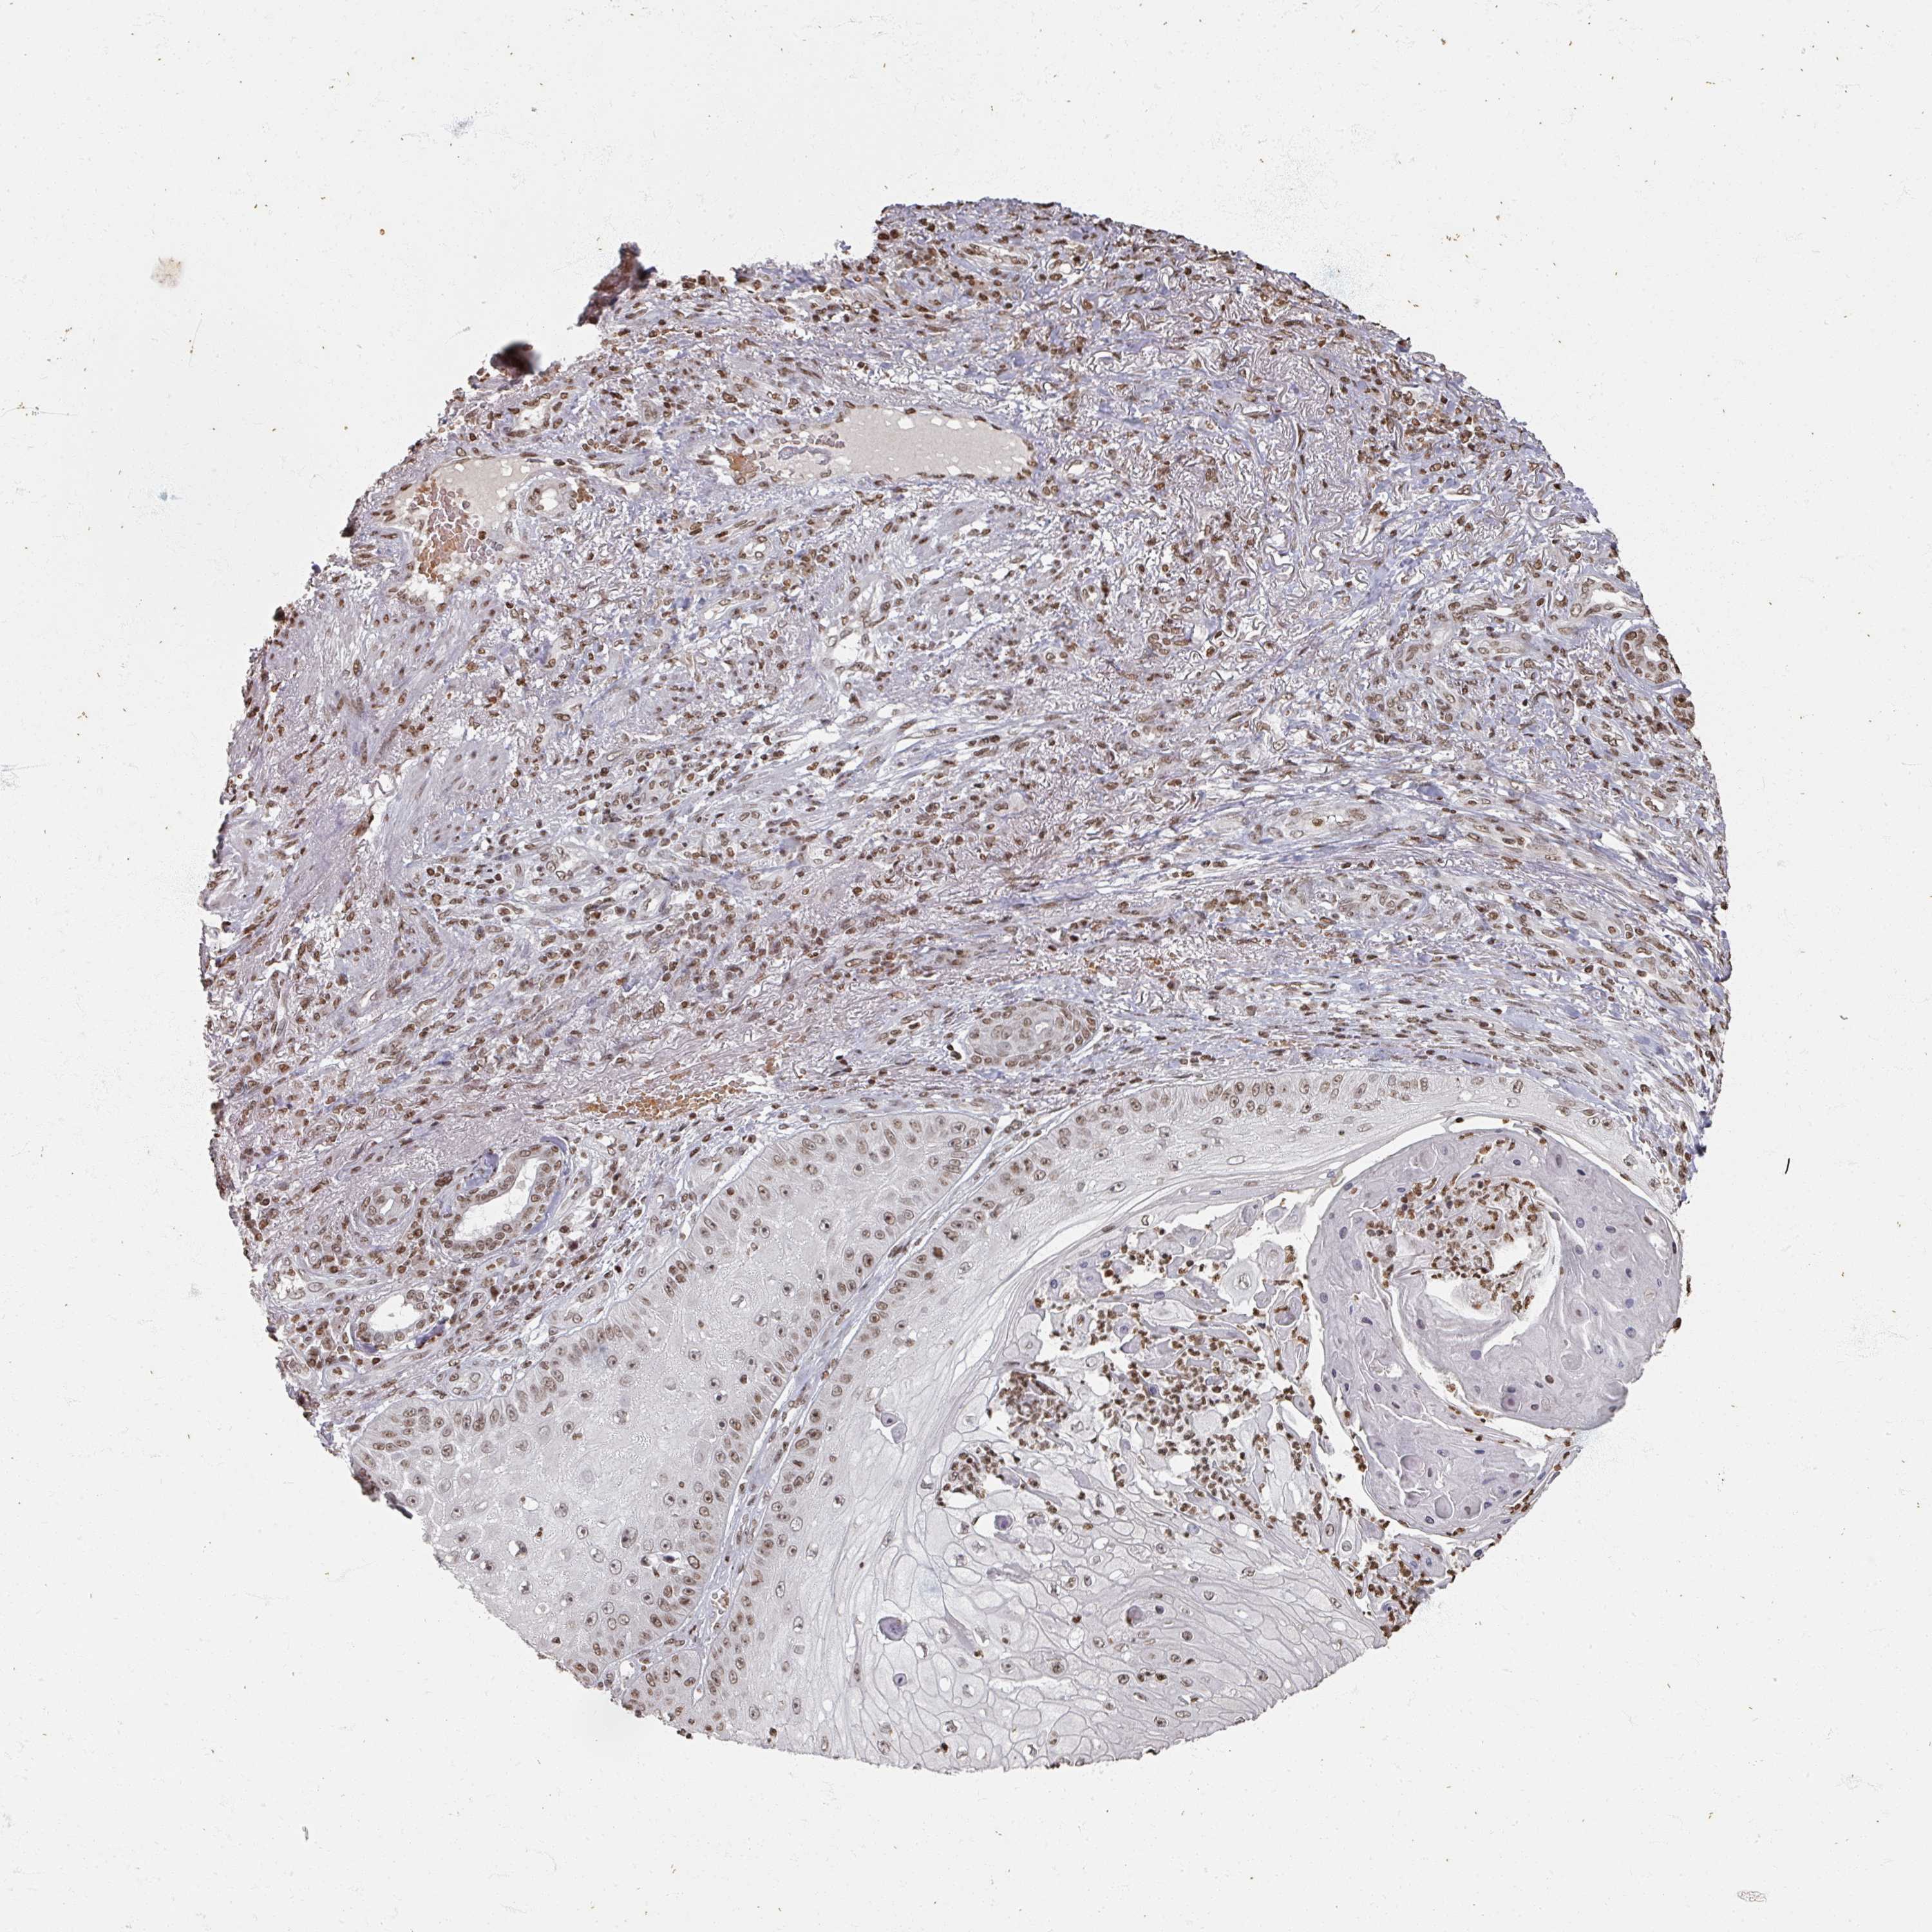

CANCER SKIN CANCER Show tissue menu

Basal cell and squamous cell cancer

SKIN CANCER - Protein expressioni

A mouse-over function shows sample information and annotation data. Click on an image to view it in a full screen mode. Samples can be filtered based on level of antibody staining by selecting one or several of the following categories: high, medium, low and not detected. The assay and annotation is described here.

Each image is clickable and will lead to virtual microscopy that enables deeper exploration of all samples and also displays staining intensity scores, fraction scores and subcellular localization as well as patient and tissue information for each sample.

Antibody HPA050863

Staining

High

Medium

Low

Not detected

Intensity

Strong

Moderate

Weak

Negative

Quantity

>75%

75%-25%

<25%

None

Location

Nuclear

Cytoplasmic/membranous

Cytoplasmic/membranous,nuclear

Basal cell carcinoma

Squamous cell carcinoma, NOS